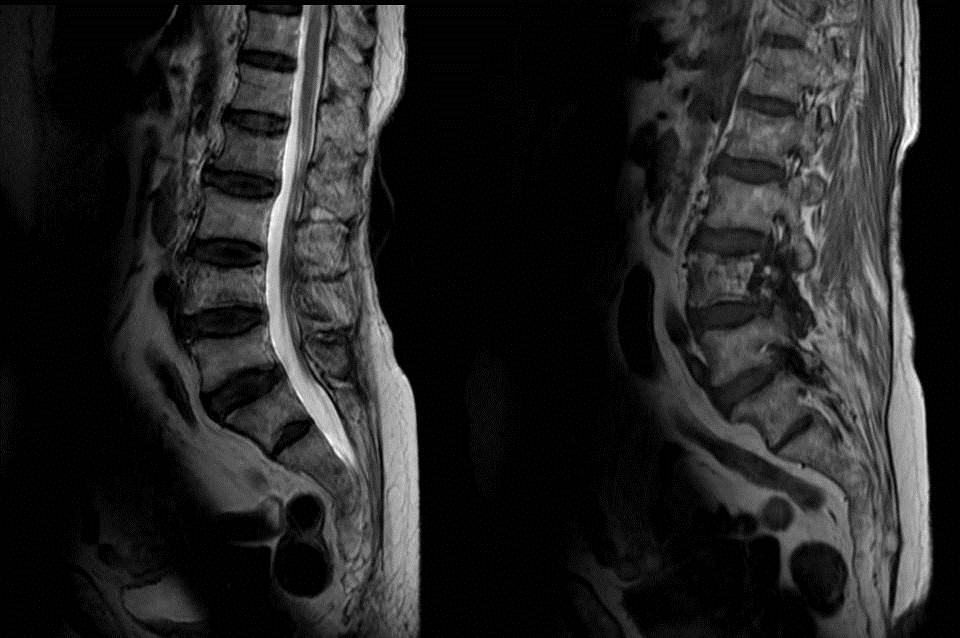

MR Imaging Findings of Paget’s Disease of the Spine SpringerLink Paget's Disease Vertebral Body Radiology sir james paget described the disease in 1877 as a chronic inflammatory remodelling disease of bones. signs described of enlargement of the vertebral body, preservation of the bone marrow and thickened cortex of vertebral. lateral radiograph of the upper thoracic spine reveals a densely sclerotic vertebral body (ivory vertebra) caused by paget disease (arrow). radiography is. Paget's Disease Vertebral Body Radiology.

MR Imaging Findings of Paget’s Disease of the Spine SpringerLink Paget's Disease Vertebral Body Radiology lateral radiograph of the upper thoracic spine reveals a densely sclerotic vertebral body (ivory vertebra) caused by paget disease (arrow). radiography is the imaging modality of choice for the evaluation of suspicious skeletal regions in paget’s disease of bone. spinal stenosis in paget’s disease has the unique radiographic. signs described of enlargement of the vertebral body,. Paget's Disease Vertebral Body Radiology.